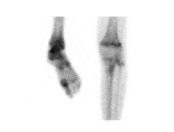

Sarcome d’Ewing

Le sarcome d’Ewing a été décrit la première fois en 1921 par James Ewing, cancérologue américain. C’est une tumeur osseuse à cellules rondes indifférenciées, plus précisément une tumeur neurœctodermique primitive. Il s’agit d’une tumeur extrêmement agressive, mais qui est très sensible à la radiothérapie. Il y aurait une translocation, c’est-à-dire une cassure ou une mutation dans les chromosomes 11 et 22. La maladie se localise principalement à la diaphyse de l’os long et parfois dans les vertèbres. La prédisposition serait 10 fois plus élevée chez les individus de race blanche plutôt que dans la population afro-américaine. Les données démographiques démontrent que ce sont les enfants qui sont les plus touchés ou les jeunes adolescents/adultes entre 5 et 20 ans, et il est extrêmement rare que ce cancer touche les gens au-delà de 20 ans. La prévalence est plus forte chez les garçons que chez les filles, et celles-ci ont de meilleurs taux de survie. Sur le plan radiographique, on décrit l’image du sarcome d’Ewing comme un « bulbe d’oignon », et la diaphyse est plutôt boursoufflée. Sur la scintigraphie osseuse (figure 1 ), la lésion apparaîtra plus

Antérieur

Postérieur